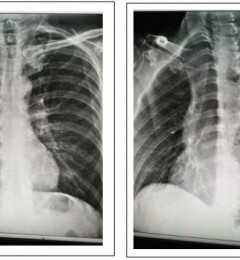

动态DR助力肺癌诊断精准高效

肺肿瘤又叫支气管肺癌(Lung.Carcinoma)是常见的恶性肿瘤之一,近数十年肺癌的发病率和死亡率都有明显增高的趋势。...【浏览全文】